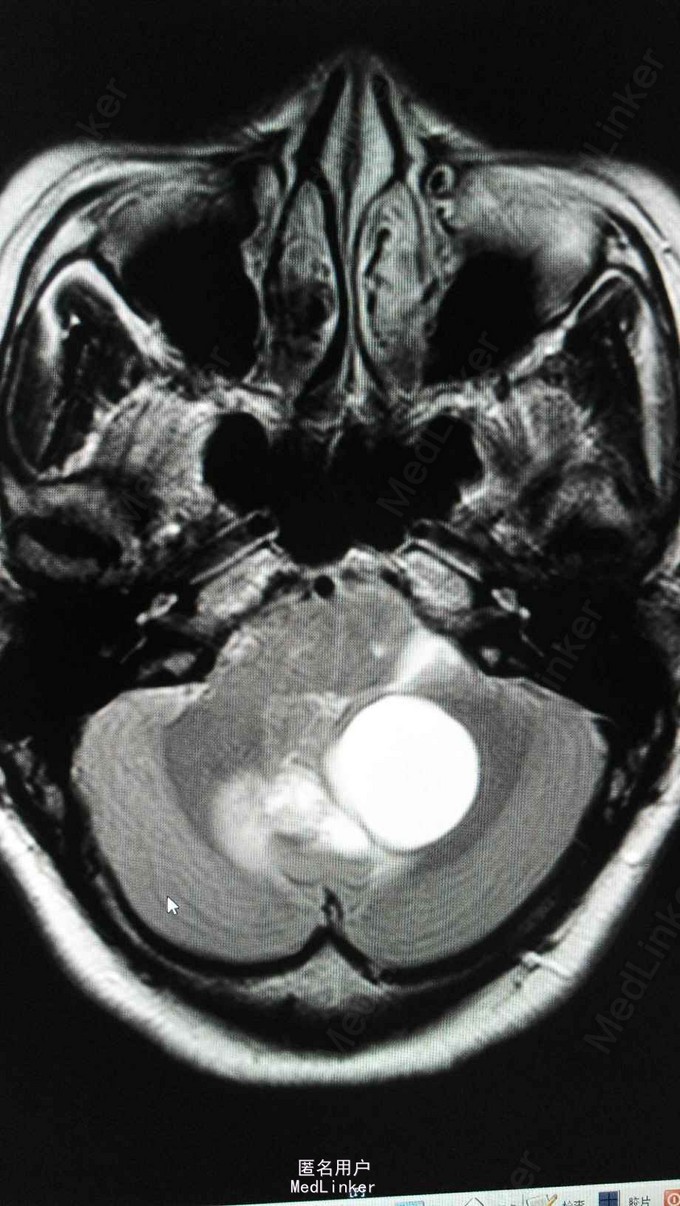

查体:T 36.5℃,P 81bpm,R 18bpm,BP 127/79mmHg;心肺腹及神经查体未及明显异常。 检查:三大常规、生化、凝血、乙肝、丙肝、梅毒、HIV未见明显异常。 头颅MRA:小脑蚓部占位,血管母细胞溜可能性大;左椎动脉颅内段局部轻度狭窄;左侧大脑前动脉A1段稍细。 腹部超声:右肾混合性占位性病变(中下极见一个大小约90*65*83mm的混合回声团,边界尚清,内回声不均,可见密集分布的无回声囊,呈蜂窝状);右肾局限性积液;胰腺内异常回声(多个大小不等的无回声囊,大者约12*11mm,边界清);双侧卵巢小囊(27*25mm(右)、25*25mm(左));肝、胆、脾未见明显异常;左肾、膀胱未见明显异常;双侧输尿管未见明显扩张;子宫未见明显异常。腹部增强CT ,胰腺多发囊性病变,右肾巨大占位,考虑肾癌。

VHL综合征 目前暂予完善相关检查及对症处理。